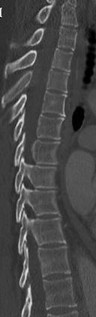

Question 24

A 65-year-old male with a known history of ankylosing spondylitis presents to the emergency department after a low-speed motor vehicle collision. A CT scan demonstrates a fracture through the C6-C7 disc space extending into the posterior elements.

What is the most appropriate surgical treatment?

Explanation